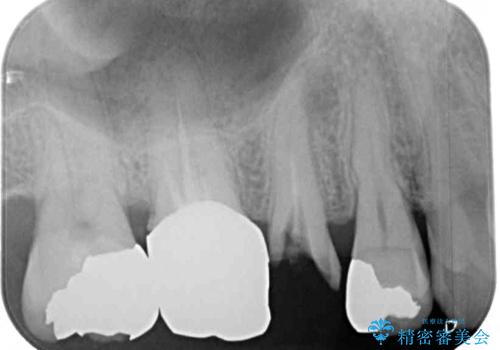

奥歯を中心に銀歯が多く装着されており、一部の歯は咬合時に痛みを感じている状態でした。

必要な歯に根管治療を行い、オールセラミッククラウンにて補綴治療を行うこととしました。

一部根管治療では症状が改善しなかったため、歯根端切除術を行いました。